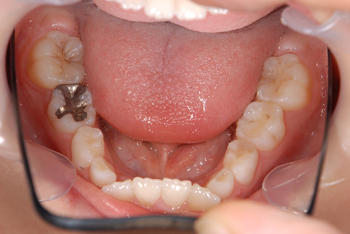

Before